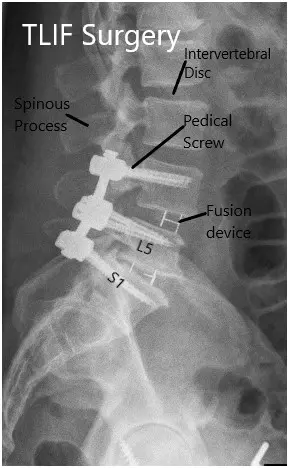

Postoperative X-ray in AP and Lateral views

Postoperative X-ray in AP and Lateral views 2

Postoperative X-ray in AP and Lateral views.